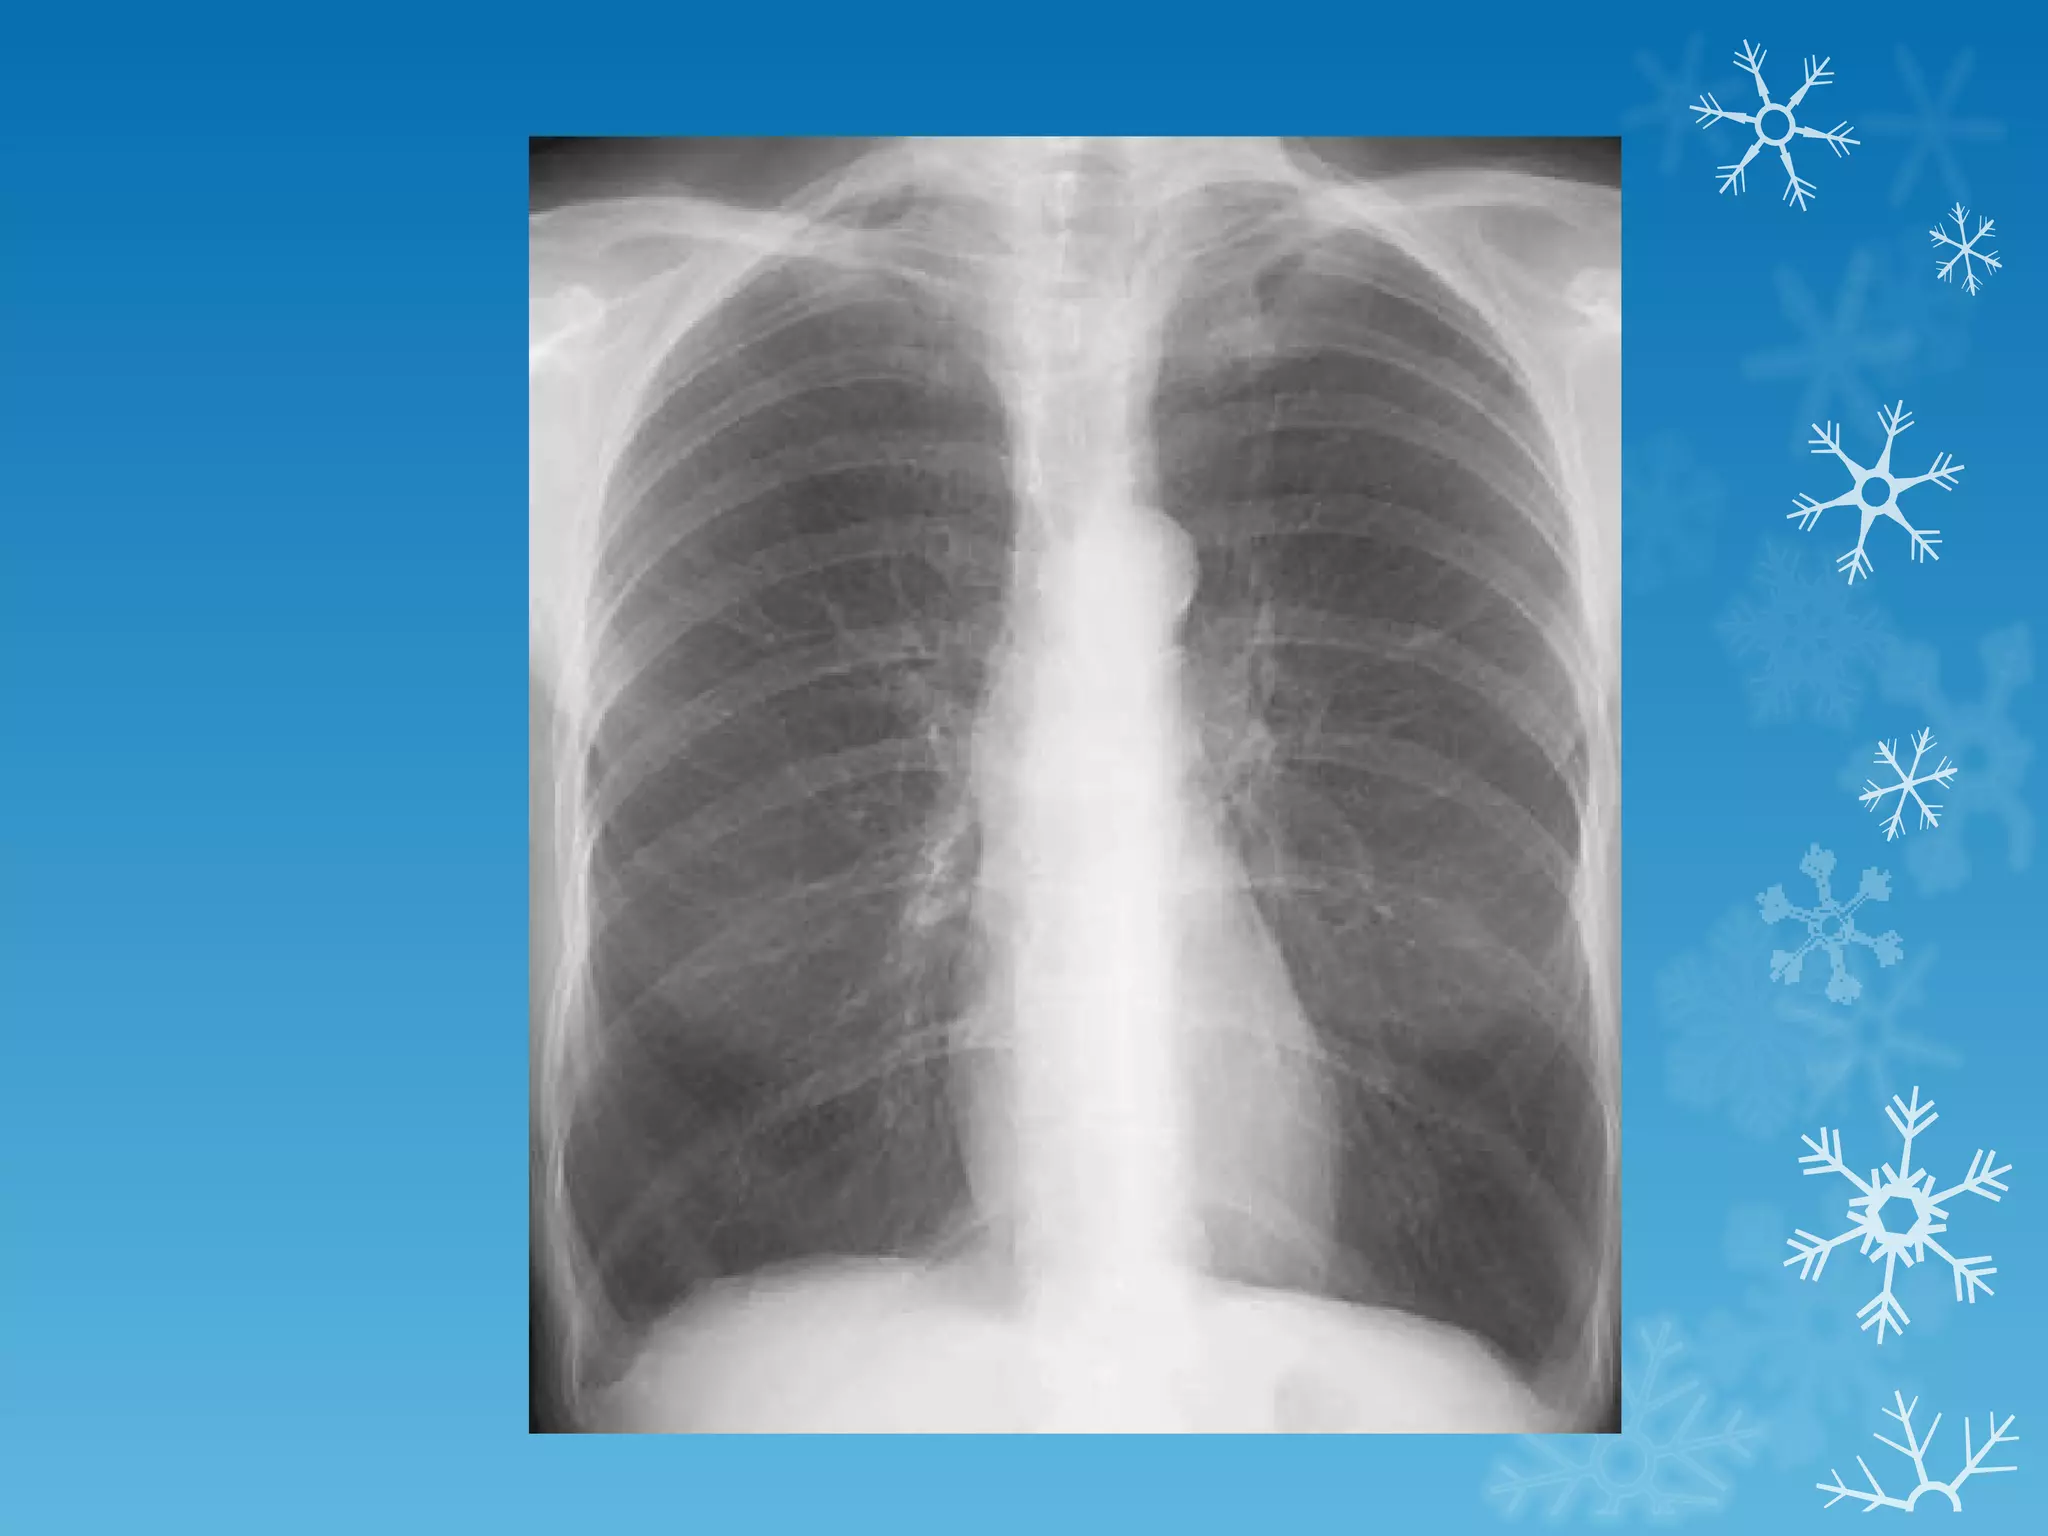

This document discusses chest x-ray interpretation and provides guidance on evaluating x-rays. It explains that tissue density determines how an x-ray beam penetrates, with denser tissues appearing whiter and less dense tissues appearing blacker. It also outlines different chest x-ray views and factors to consider like patient orientation, age, gender, and rotation. Abnormalities are described as appearing too white, too black, too large, or in the wrong place. The document stresses a systematic approach of identifying, localizing, describing lesions, and providing differential diagnoses.